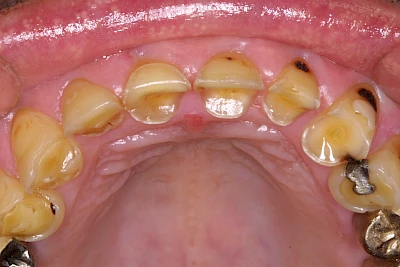

Auswaschung (Erosion) dagegen ist eine Verschleißerscheinung der Zähne aufgrund von immer wiederkehrenden Säureangriffen durch die Nahrung, verstärkt zum Beispiel durch den Genuss säurehaltiger Getränke oder Speisen. Auch bei Menschen mit einer Essstörung (z. B. Bulimie) können die Zähne durch die Magensäure ausgewaschen erscheinen.